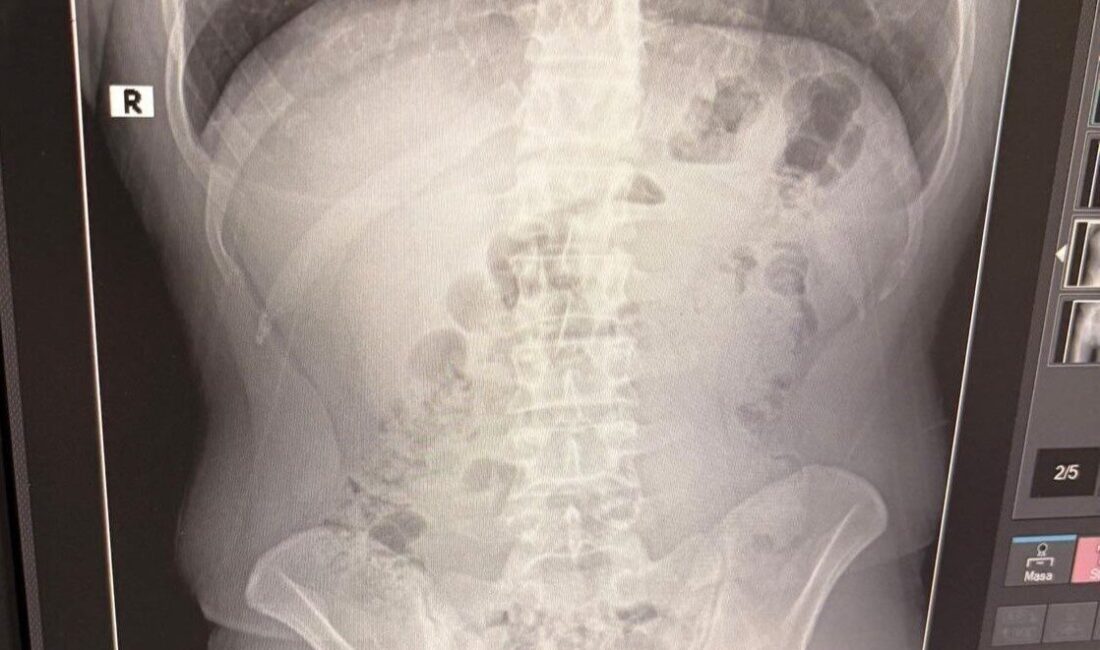

Gözaltına alınan şahısların adreste gerçekleştirilen arama sırasında, şüphelilerden birinin üzerinde bir kapsül bulundu. Şüpheler artınca, tüm şahıslar hastaneye sevk edildi ve röntgen muayenelerinde mide içeriklerinde kapsül şeklinde gizlenmiş metamfetamin tespit edildi.

Hastanede tedavi altına alınan şüphelilerin vücutlarından çıkarılan kapsüllerle birlikte toplam 1 kilo 516 gram metamfetamin ele geçirildi. Ele geçirilen uyuşturucu maddelere el konulurken, şüpheliler emniyetteki işlemlerinin tamamlanmasının ardından adliyeye sevk edildi. Çıkarıldığı mahkemede tutuklanan Y.T., A.T. ve M.J., cezaevine gönderildi.